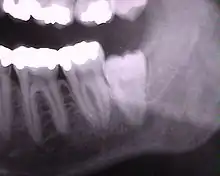

Правильная диагностика является определяющим фактором успеха лечения ретенированных зубов. Адекватное клиническое обследование и рентгенография современным ортопантомографом позволяет определить положение ретенированного зуба, что способствует оптимальному выбору хирургической методики.

Самым проблемным случаем являются ретенированные зубы мудрости на верхней и нижней челюстях. Зубы мудрости редко растут правильно, чаще они пытаются прорезаться под углом или горизонтально по отношении к остальному зубному ряду. Это приводит к давлению на соседние зубы и их разрушению со временем. Данную патологию можно диагностировать на 3D-томографии — она ясно показывает расположение ретенированных зубов мудрости.